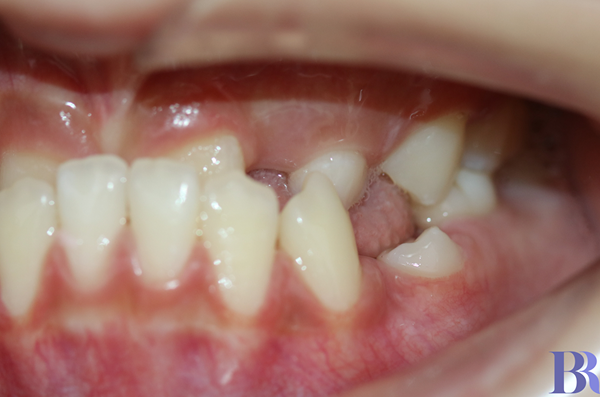

교정 전 왼쪽 모습

교정 전 좌측 모습입니다

앞니로 음식물을 제대로

끊어 먹을수도 없고

어금니도 잘 맞물리지 않네요.